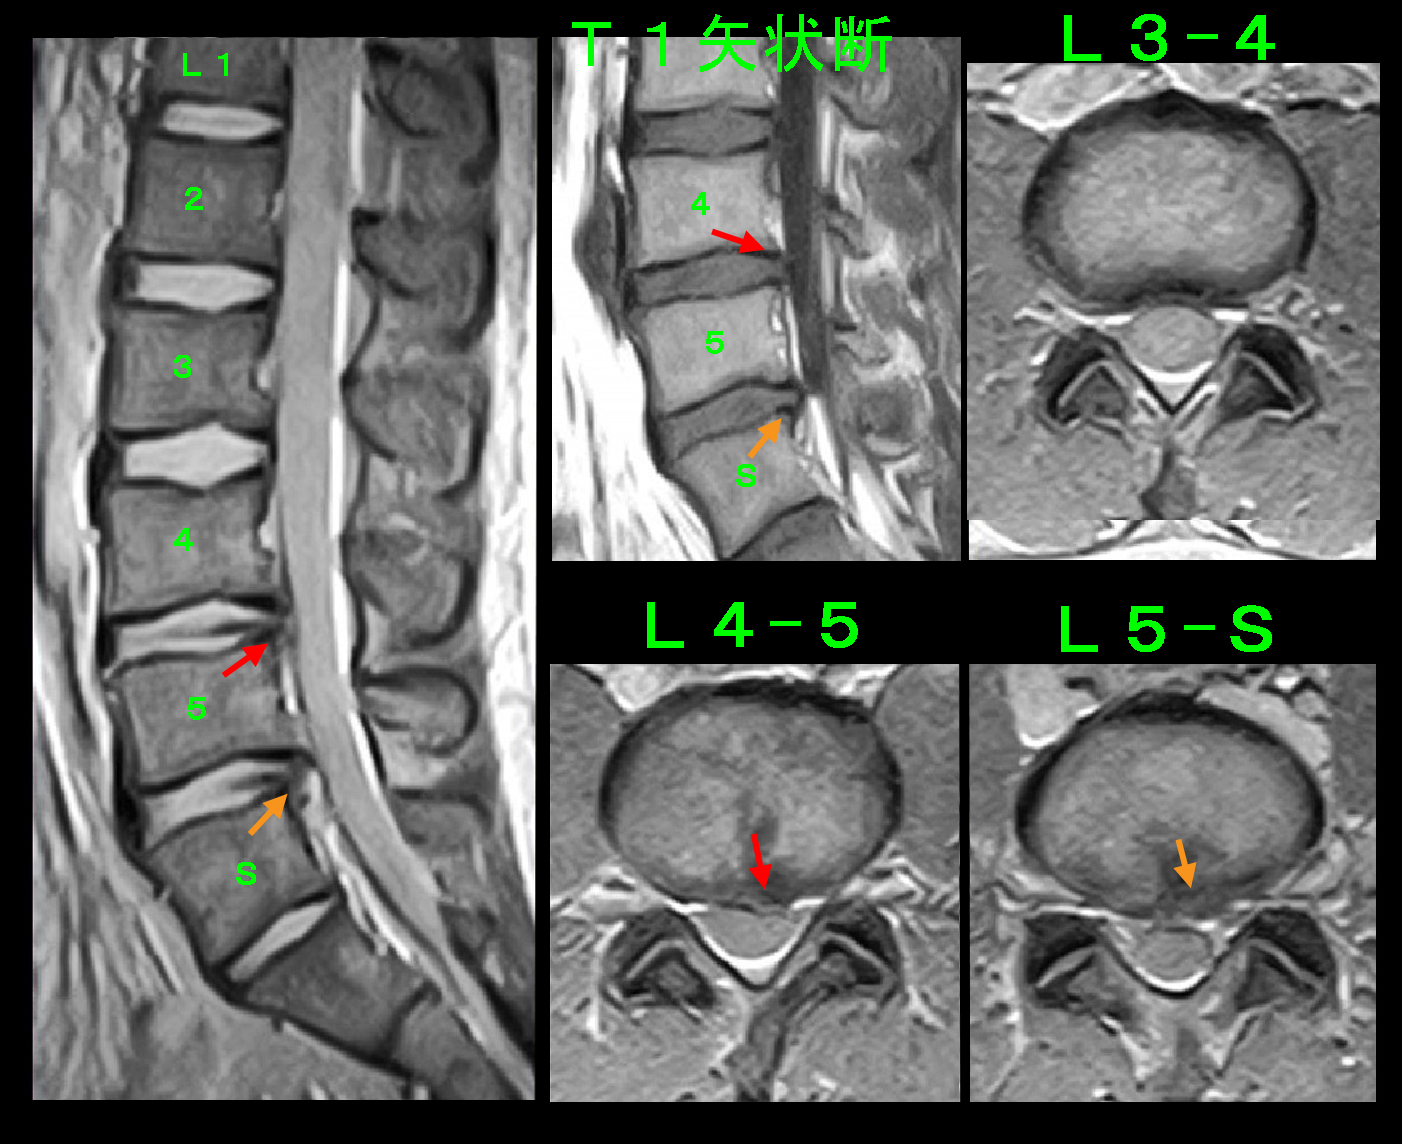

25才男 MR2.jpg

同日のMRI検査では、前回の責任高位であったL45(赤矢印)とは異なるL5Sの椎間板ヘルニア(オレンジ矢印)が悪化していることが確認されました。

そこで、L5S高位での両側の神経根ブロックを施行しています。